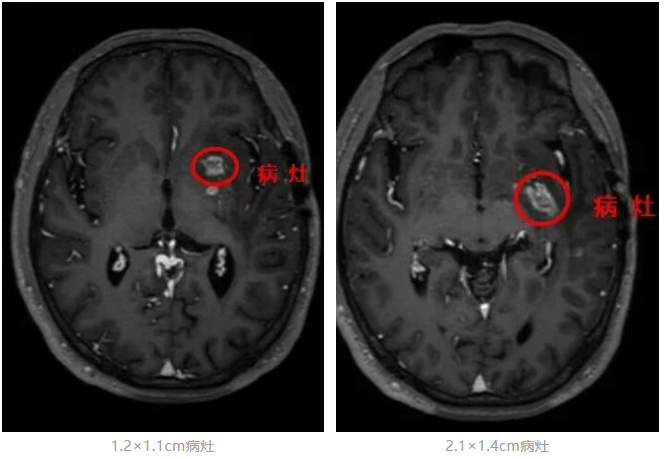

术前,孙新林教授团队利用多模态影像规划软件,精确设计穿刺路径和消融范围;术中,在机器人辅助下将光纤沿着预设的“安全通道”,精准置入大脑深处的病灶靶点,并在MRI实时监控下10分钟完成激光消融。

术前精准规划穿刺路径和消融范围

机器人辅助下将光纤精准置入靶点

MRI实时监控下完成精准完成激光消融